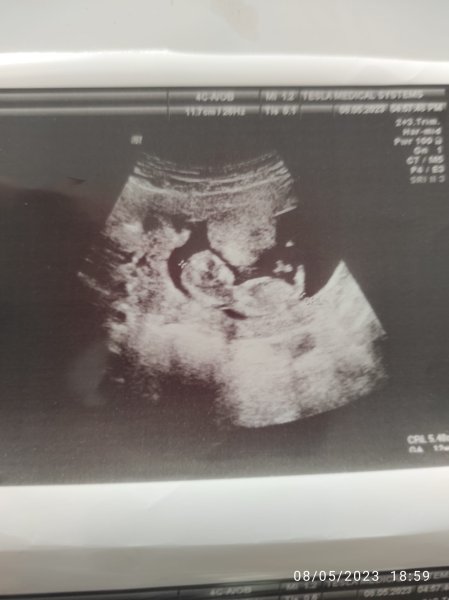

Net olmamakla birlikte ilgili bölgedeki çıkıntıya baktığımda kız gibi görünüyor. Rabbim hayırlısını nasip etsin. Bu tahmin yüzde yüz değildir bilginiz olsun 🙂

Vallahi ben uzman değilim ve Gaybı geleceği olacağı ancak Allah bilir ha illa yüzde verin diyor iseniz %52 kız diyelim![]()